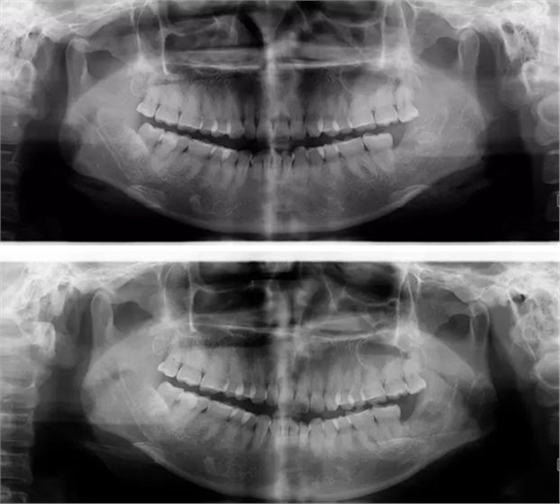

遇到斷根怎么辦?我的觀點(diǎn):拔!但有個(gè)前提,必須保證安全,否則寧可保留,因此拔牙前的溝通很重要!